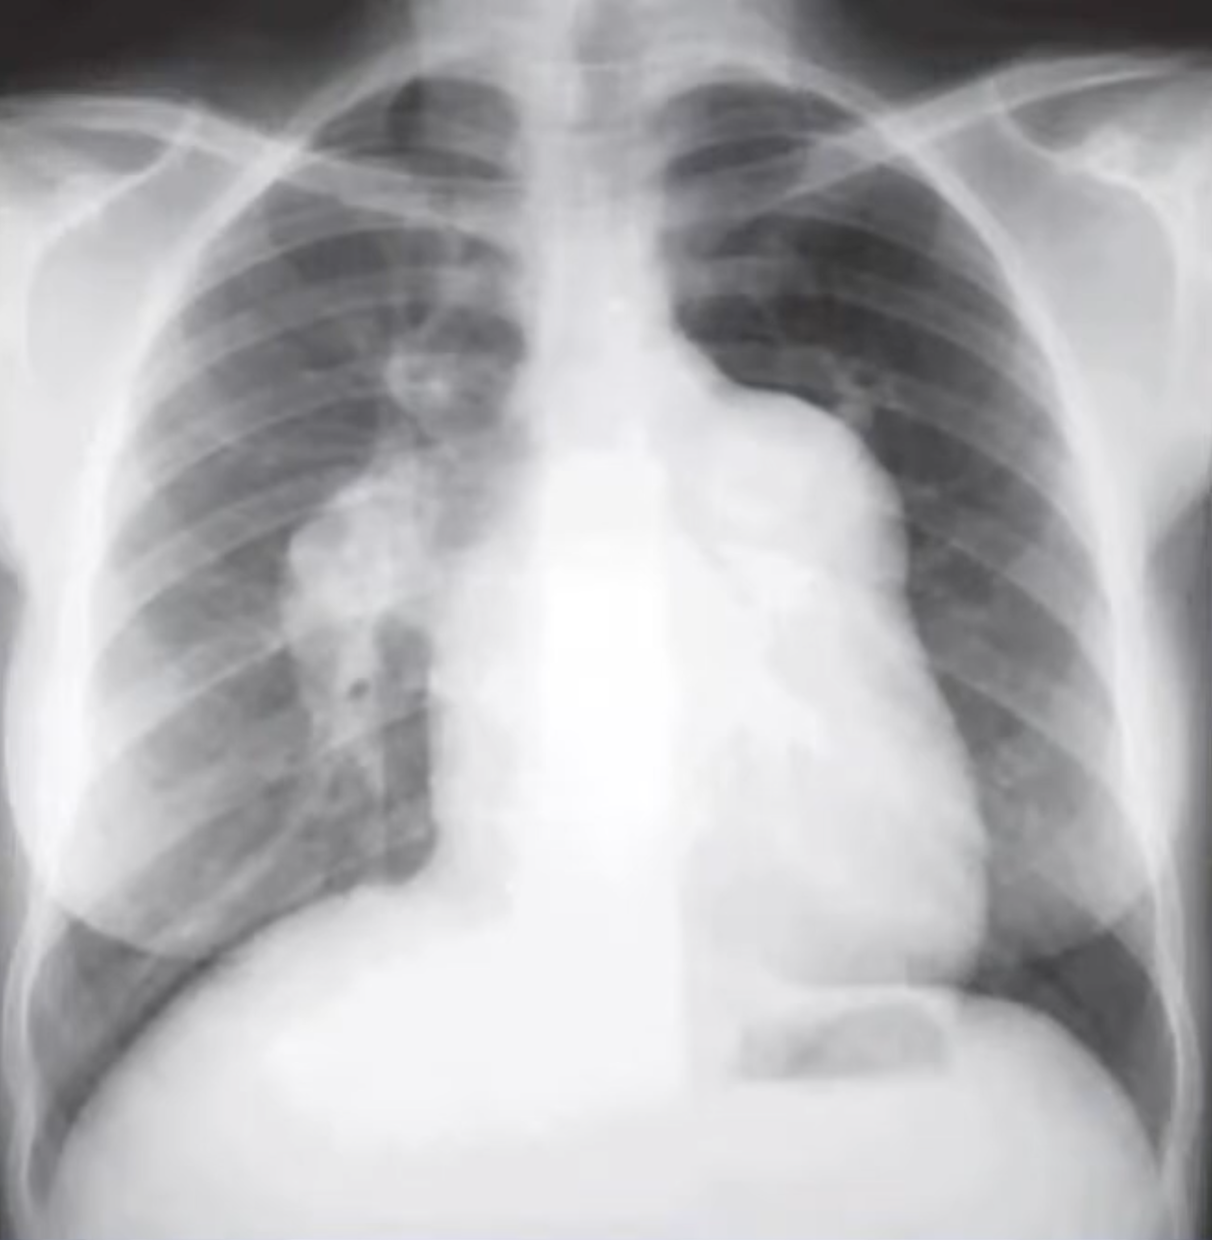

Hipertensão arterial pulmonar

Sinais radiológicos da HAP

A

• Dilatação de artéria pulmonar central

• Estreitamento abrupto ou afilamento de vasos pulmonares

• Aumento de VD e AD

• Dilatação de artérias brônquicas

• Atenuação em mosaico (perfusão pulmonar)

Sinais de hipertensão arterial pulmonar